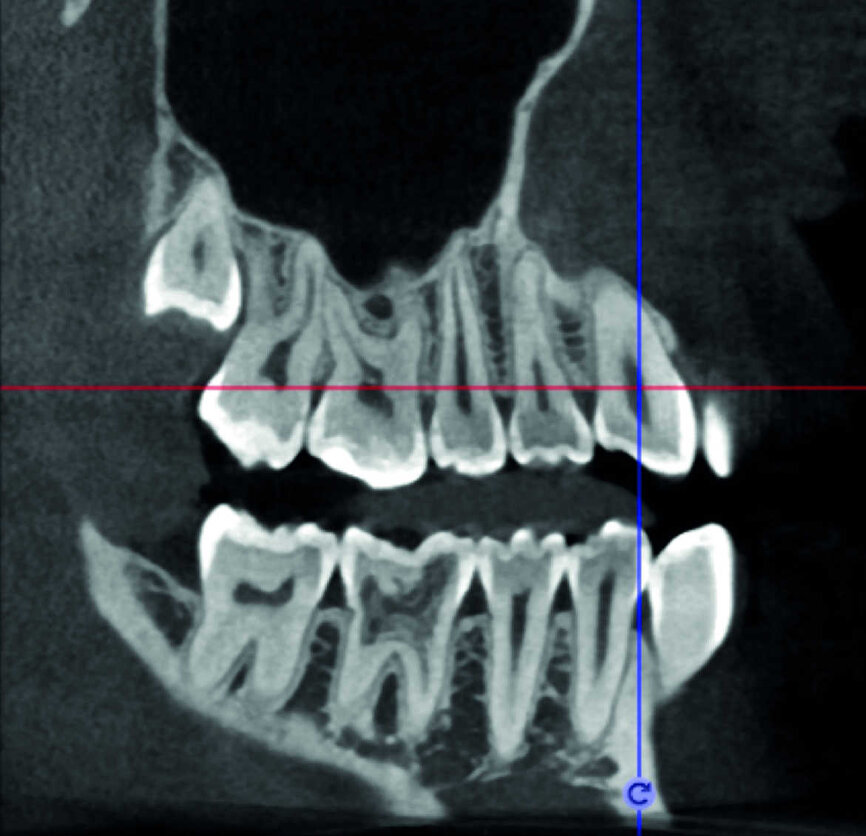

Le cas avec lequel je souhaite commencer mon exposé clinique est un exemple parfait de la difficulté à définir l’origine des symptômes d’un patient, par l’examen d’une simple radiographie intraorale. Non seulement l’examen 2D ne permet pas d’établir avec certitude la présence d’une lésion, mais surtout, il est impossible d’en déterminer la taille, la morphologie et le type. Au contraire, une analyse de l’imagerie 3D offre une image claire de la situation clinique. Chez ce patient, les coupes coronales et sagittales révèlent la présence d’une importante lésion s’étendant de l’apex de la racine mésiale de cette molaire jusqu’à la zone de furcation, tandis que les coupes axiales nous permettent d’analyser précisément l’anatomie endodontique et, en particulier, la forme de la racine mésiale, qui apparaît fusionnée avec la racine palatine. Un panorama complet du cas peut donc guider le processus de décision et orienter le plan de traitement vers une modalité bien précise de traitement (Figs. 1–4).